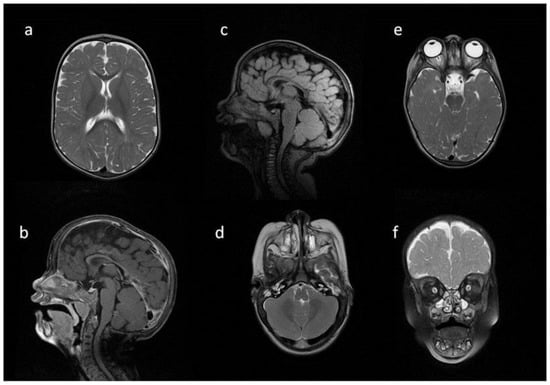

| Patient No | 1 | 2 | 3 | 4 | 5 | |

|---|---|---|---|---|---|---|

| age at exam | 4 mo | 3 yo | 1 y 2 mo | 1 y 11 mo | 3 y 2 mo | 14 yo |

| radiological imaging | ||||||

| WM signal abnormalities | + | + | + | |||

| areas of delayed myelination | + | + | + | + | + | |

| enlarged perivascular spaces | + | + | + | + | ||

| narrow corpus callosum | + | +/− | + | + | ||

| prominent ventricular system | +/− | + | +/− | + | + | |

| arachnoid cyst | + | + | ||||

| optic nerve sheath enlargement | + | + | ||||

| J-shaped sella turcica | + | + | + | +/− | + | +/− |

| craniocervical junction distortion | + | +/− | + | + | ||

| posterior fossa horns | + | + | + | + | ||

| fluid effusion temporal bone | + | + | + | + | +/− | |

| closed sagittal suture | + | + | + | |||

| vertebral bodies deformity | + | + | ||||

| intervertebral disc anomalies | + | + | ||||